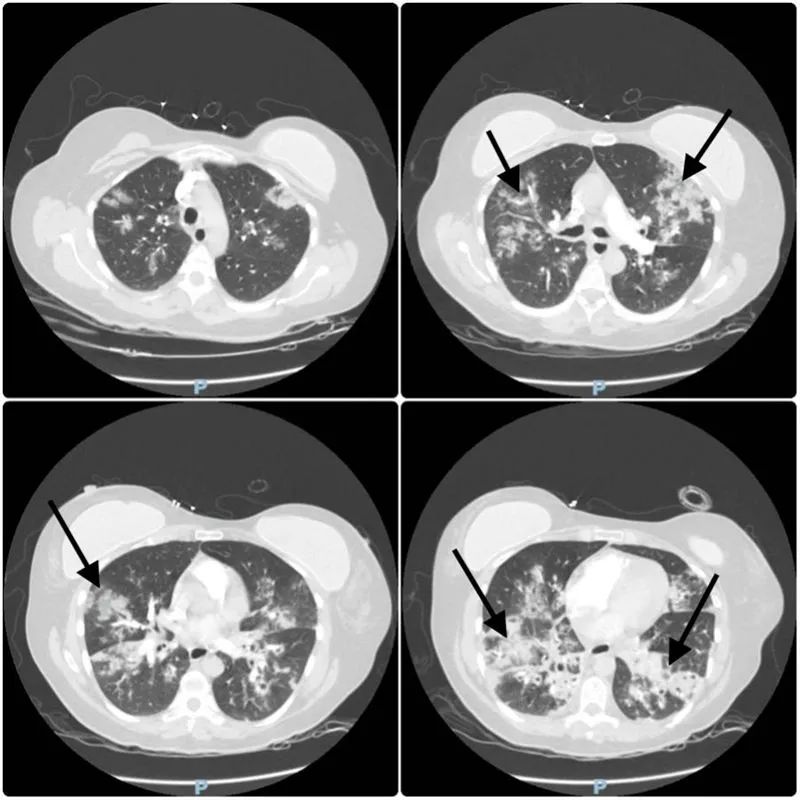

警惕,无明显危险因素的甲流患者也可发生急性呼吸窘迫综合征!

病史摘要:52 岁女性,主因严重突发性呼吸困难、胸部不适、咽喉疼痛就诊。就诊前一周有流涕、咳嗽等症状,前一天因咽喉疼痛加重就诊,甲型流感阳性,对症治疗及用奥司他韦后出院。既往有血脂异常、偏头痛、两年前轻微创伤性颅内出血(保守治疗无后遗症)。 诊疗过程:此次就诊呼吸急促、心动过速、血氧饱和度下降,听诊双侧进气良好伴弥漫性干啰音。动脉血气提示呼吸性碱中毒和缺氧,胸部 X 线和 CT 显示双侧斑